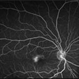

- 60 year old female with an end-stage proliferative macular telangiectasia type 2 with right-angle retinal vessels, manifested as blunted arterioles and venules that connect the superficial and deeper retinal plexus, chorioretinal anastomosis with a fibrovascular scar and a typical retinal pigment hyperplasia , fellow eye showed a focal discontinuity in the ellipsoid zone with a loss of the outer and a disorganization of the inner retinal layers, not involving the foveal center and a non exudative neovascularization